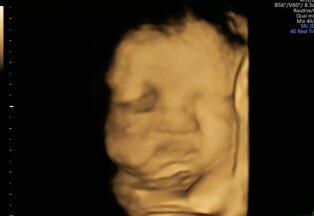

ลูกสาวจ้า กำหนดคลอด 1 พ.ย.

อัลตร้าซาวด์แบบนี้เท่าไหร่คะ